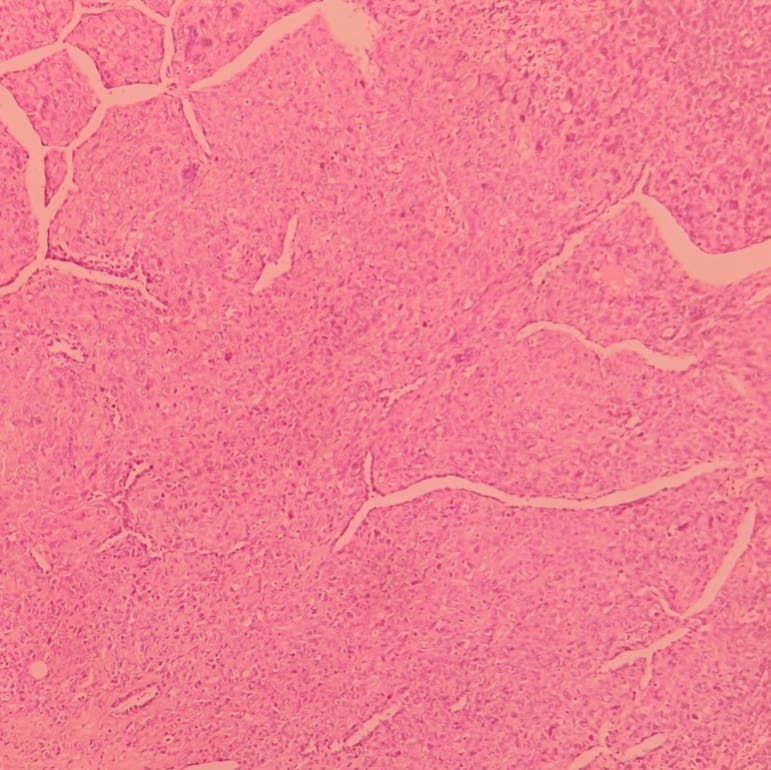

Caption: History of uterine leiomyosarcoma and metastasis to lung, again with multiple lung metastases.. In microscopic exam prominent pleomorphism and easily indentifiable mitotic figures including atypical ones are noted. Staghorn vessels are found all throughout the tumor.